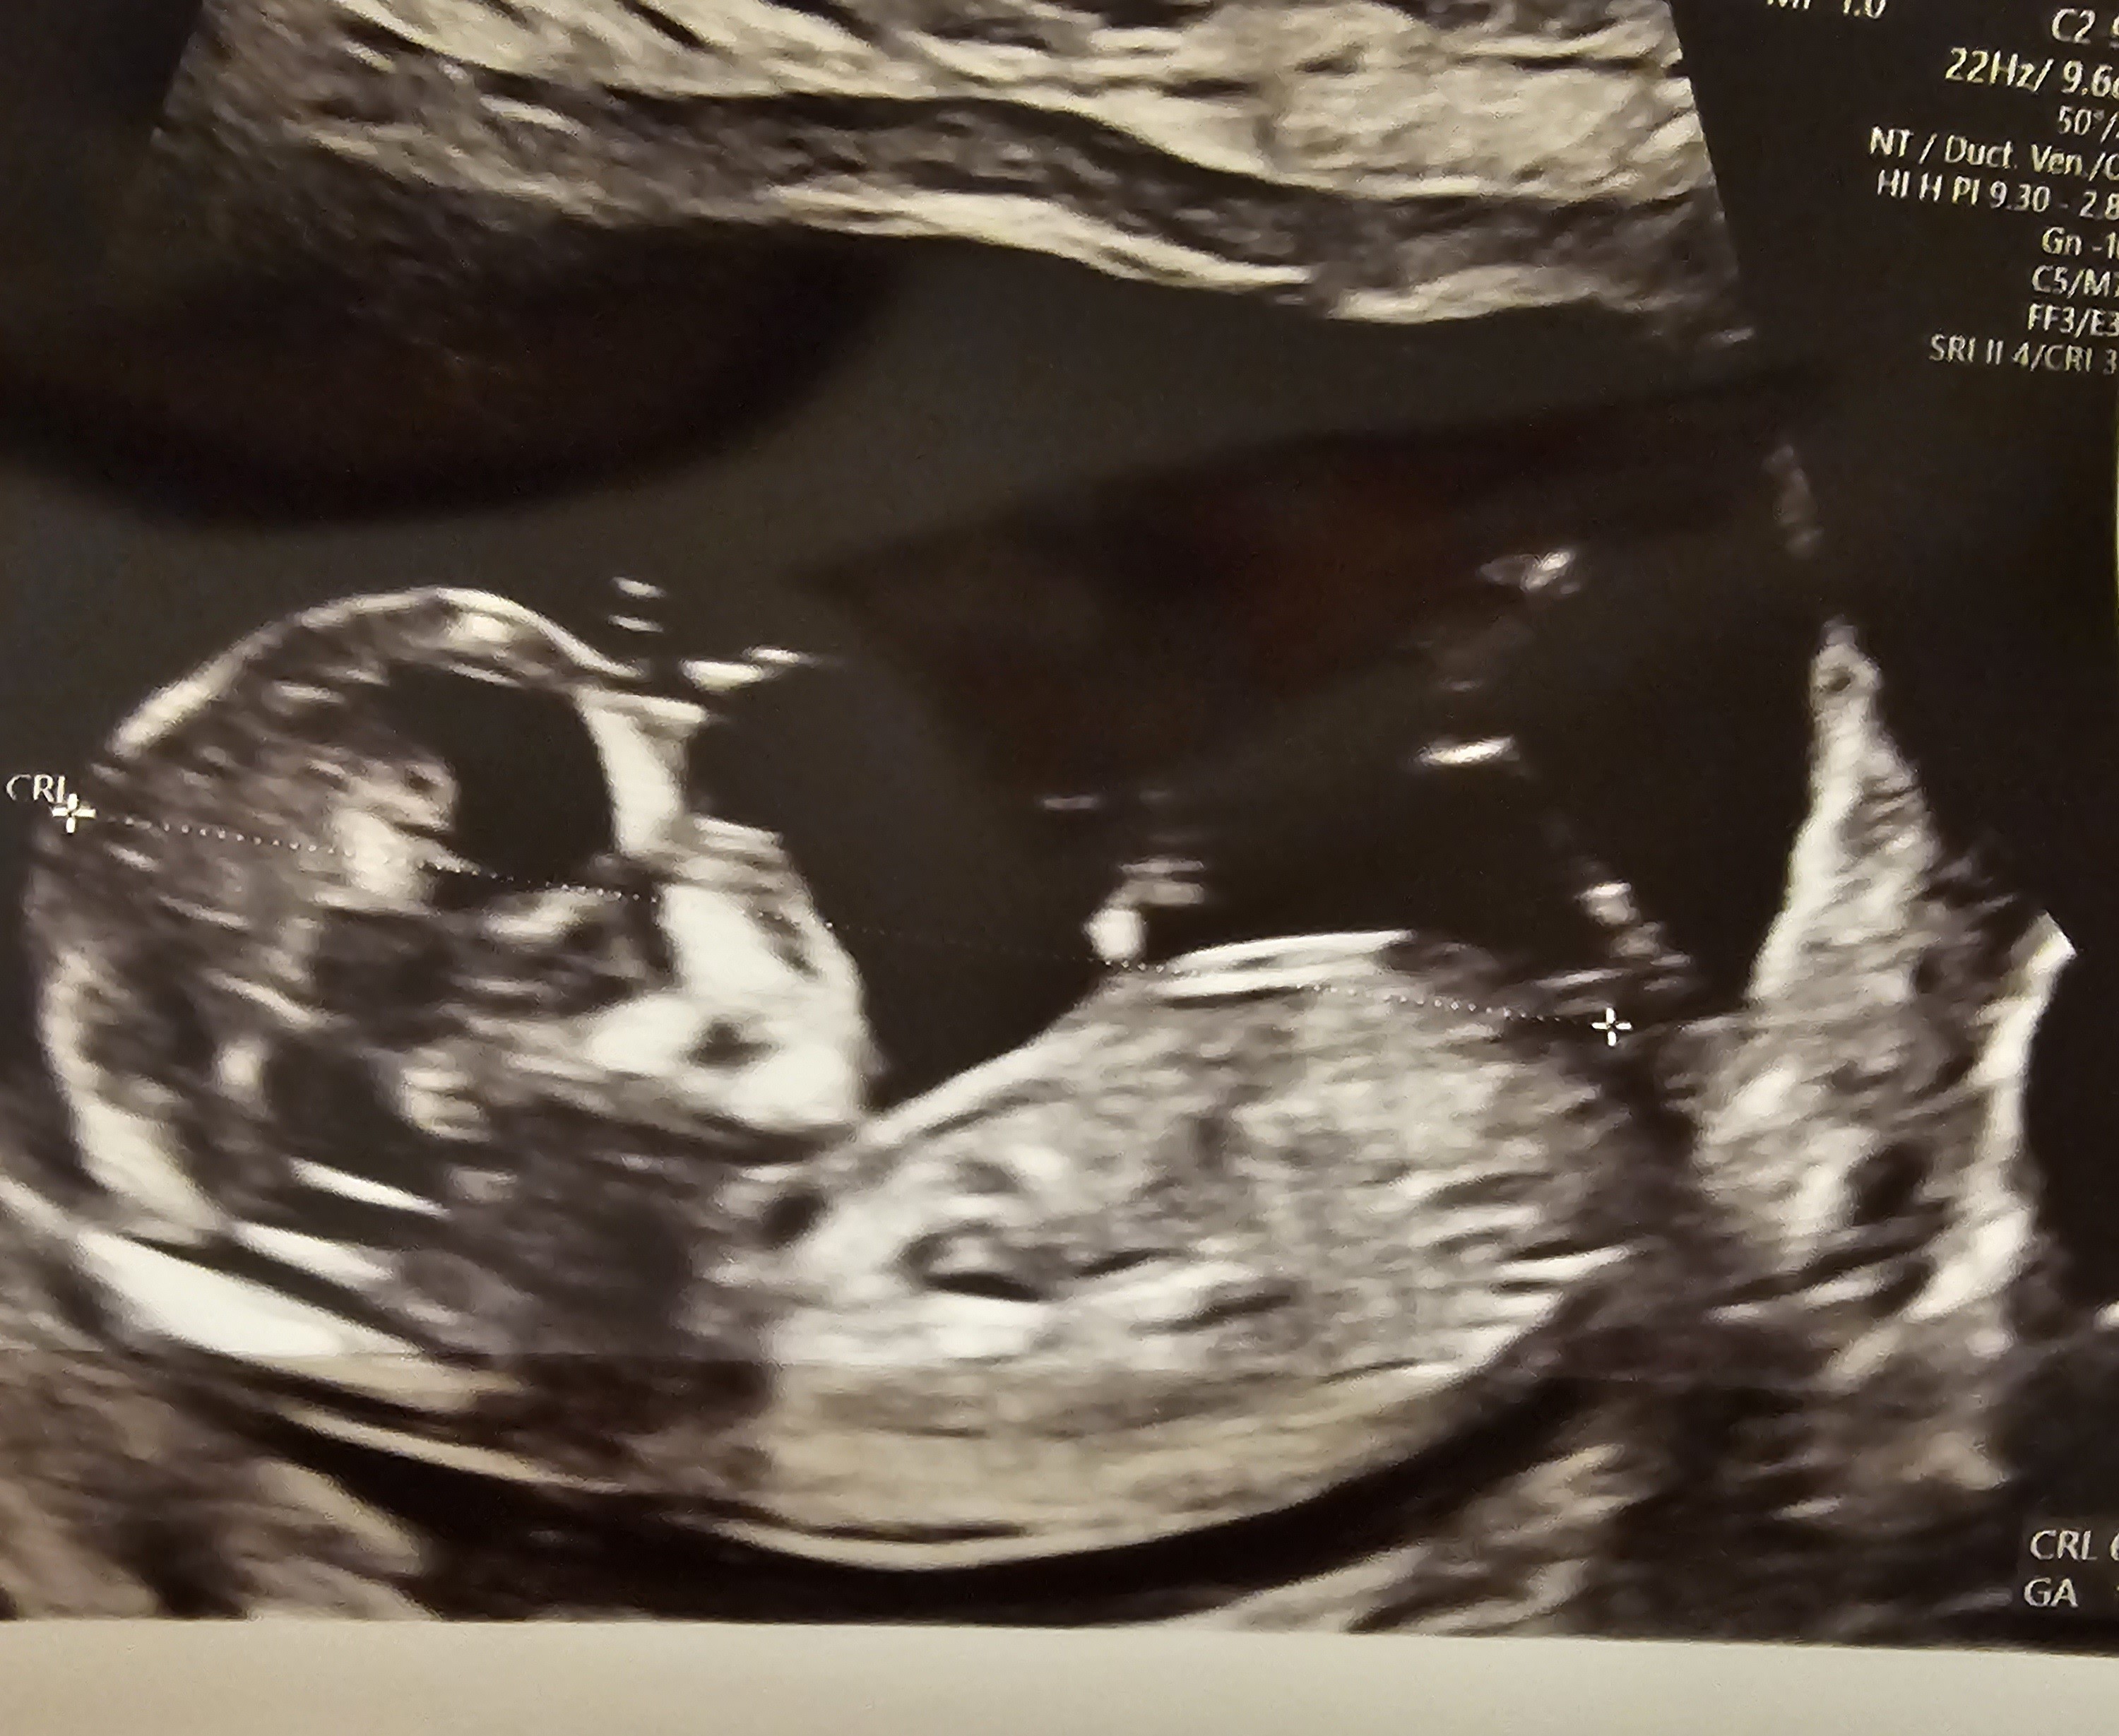

Hej kochane. Czy ktoś zagląda tutaj? I mógłby coś powiedzieć wg tych zdjęć 🙂

• 20241112_174040.jpg

20241112_174040.jpg

953,5 KB · Wyświetleń: 310

• 20241112_174014.jpg

20241112_174014.jpg

904,6 KB · Wyświetleń: 297

• 20241112_174011.jpg

20241112_174011.jpg

1,4 MB · Wyświetleń: 288